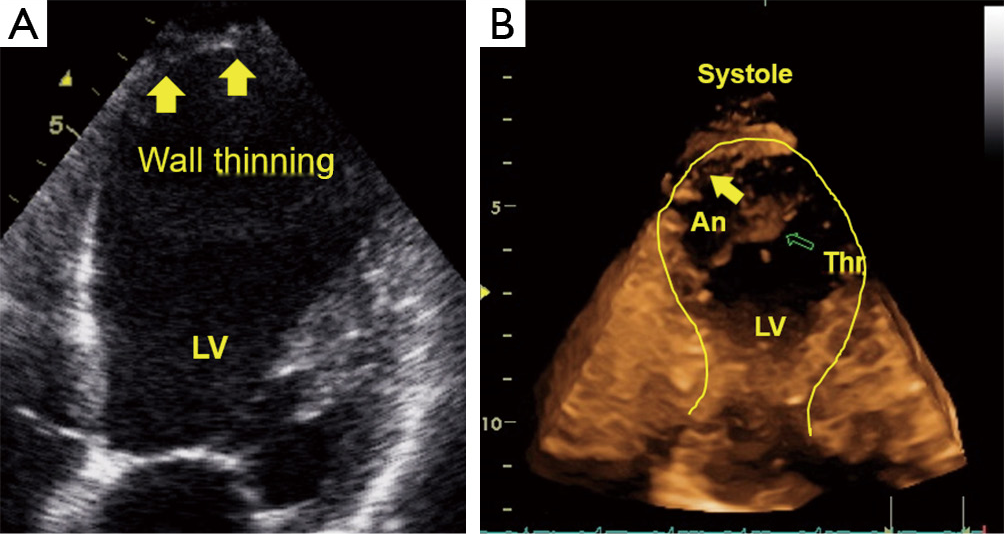

Thinning of the left ventricular wall and rupture. Myocardial Heart Wall Thinning Treatment Cardiomyopathy is a progressive disease of the myocardium, or heart muscle. Robert bonow, md, max and lilly goldberg distinguished professor of cardiology, director of the. Thinning of heart muscle wall potentially reversible. Treatment options for cardiomyopathy include lifestyle changes, medications, and surgery. Refractory hcm is traditionally addressed through a septal myectomy, which restores normal systole dynamics and provides almost immediate. Heart Wall Thinning Treatment.

Severe Left Ventricular Wall Thinning and Extensive Fibrosis Without Heart Wall Thinning Treatment Most people with hcm can live a normal life. Treatment includes medicines and sometimes surgically implanted devices and heart surgery. Cardiomyopathy is a progressive disease of the myocardium, or heart muscle. Refractory hcm is traditionally addressed through a septal myectomy, which restores normal systole dynamics and provides almost immediate relief of symptoms. Hypertrophic cardiomyopathy (hcm) is a disease that involves. Heart Wall Thinning Treatment.

Echocardiographic assessment of myocardial ischemia Leischik Annals Heart Wall Thinning Treatment Hypertrophic cardiomyopathy (hcm) is a disease that involves the thickening of your heart muscle. Cardiomyopathy is a progressive disease of the myocardium, or heart muscle. Treatment options for cardiomyopathy include lifestyle changes, medications, and surgery. Refractory hcm is traditionally addressed through a septal myectomy, which restores normal systole dynamics and provides almost immediate relief of symptoms. Robert bonow, md, max. Heart Wall Thinning Treatment.